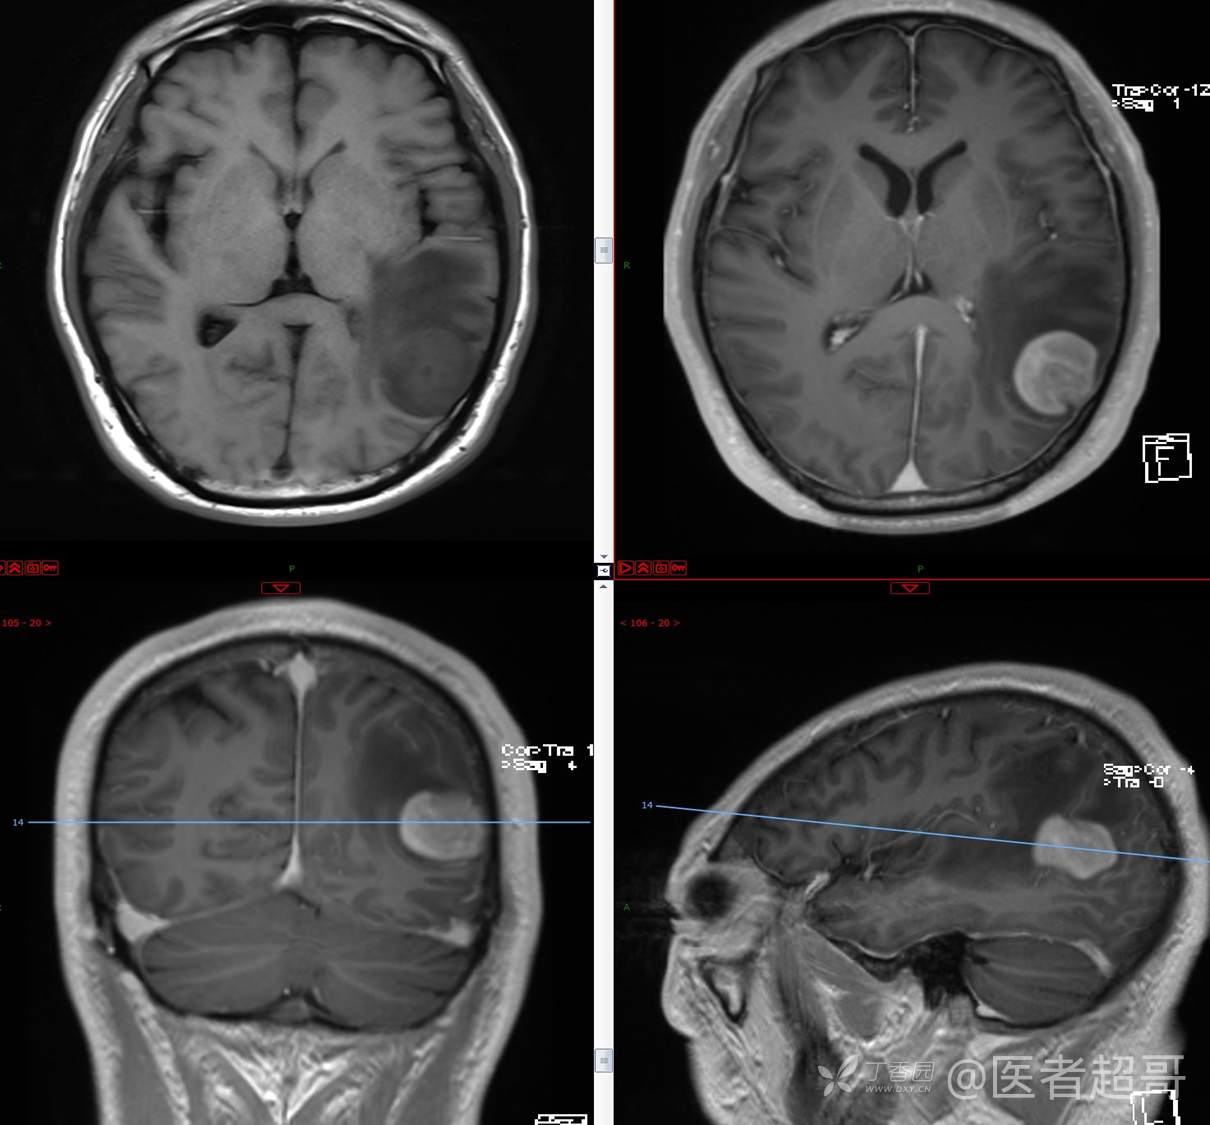

比较典型病例,CT、MRI齐全,请分析,领丁当!

男,56岁

主 诉:查体发现颅内占位10天。

现病史:患者于约10天前于我院查体时行颅脑MRI提示左侧顶叶占位病变,无头痛头晕,无恶心呕杜,无肢体活动不利,无感觉异常,现患者为求进一步治疗,就诊于我科门诊,门诊以“颅内占位性病变”收入我科。患者自发病以来,神志清,精神可,饮食及睡眠差,大小便无明显异常,体重无明显变化。